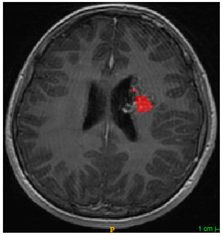

Three cases from the NTUH dataset showing representative results of different models were shown in Table 2, Table 3 and Table 4. The overall dice scores of these networks on the NTUH dataset ranged from 0.33 (DeepMedic) to 0.51 (V-Net). Table 5 shows the detailed performance of each network tested with the NTUH dataset.

Table 2.

Predictions with low dice scores.

Table 3.

Predictions with average dice scores.

Table 4.

Predictions with high dice scores.